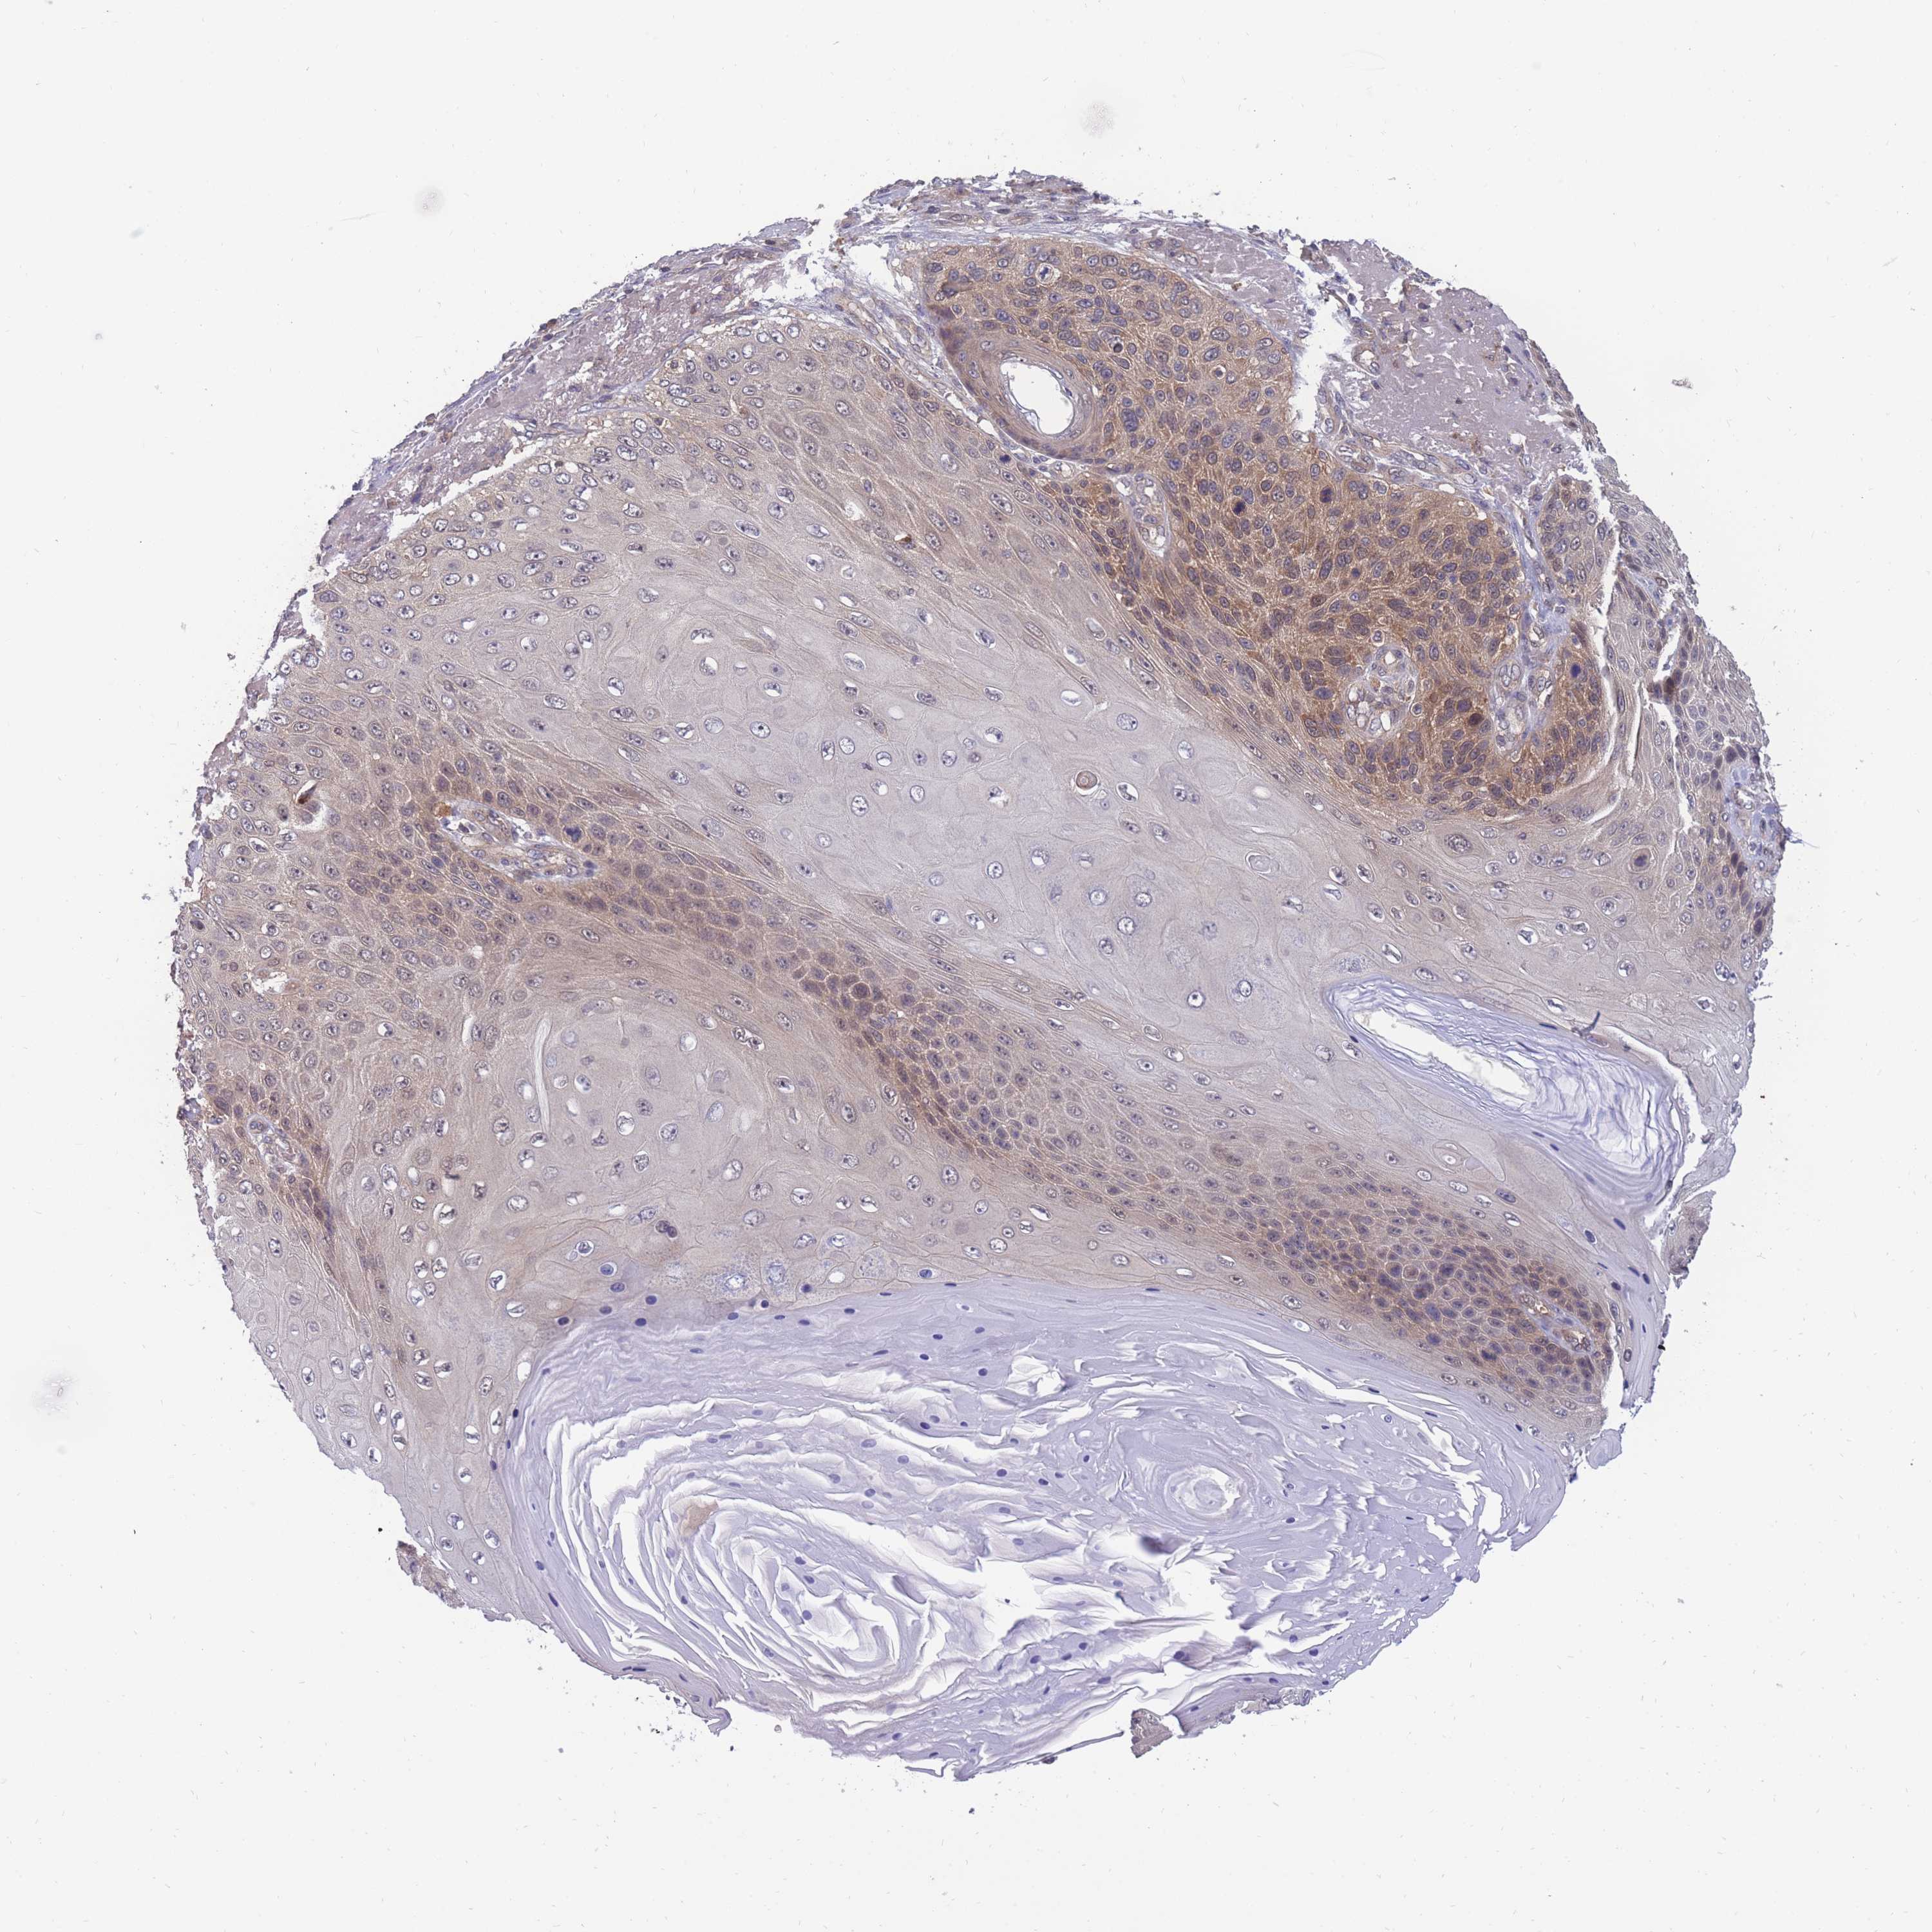

SKIN CANCER - Protein expressioni

A mouse-over function shows sample information and annotation data. Click on an image to view it in a full screen mode. Samples can be filtered based on level of antibody staining by selecting one or several of the following categories: high, medium, low and not detected. The assay and annotation is described here.

Antibody stainingi

Antibody staining in the annotated cell types in the current human tissue is reported as not detected, low, medium, or high, based on conventional immunohistochemistry profiling in selected tissues. This score is based on the combination of the staining intensity and fraction of stained cells.

Each image is clickable and will lead to virtual microscopy that enables deeper exploration of all samples and also displays staining intensity scores, fraction scores and subcellular localization as well as patient and tissue information for each sample.

Antibody HPA044976

Staining

High

Medium

Low

Not detected

Intensity

Strong

Moderate

Weak

Negative

Quantity

>75%

75%-25%

<25%

None

Location

Nuclear

Cytoplasmic/membranous

Cytoplasmic/membranous,nuclear

Squamous cell carcinoma, metastatic, NOS